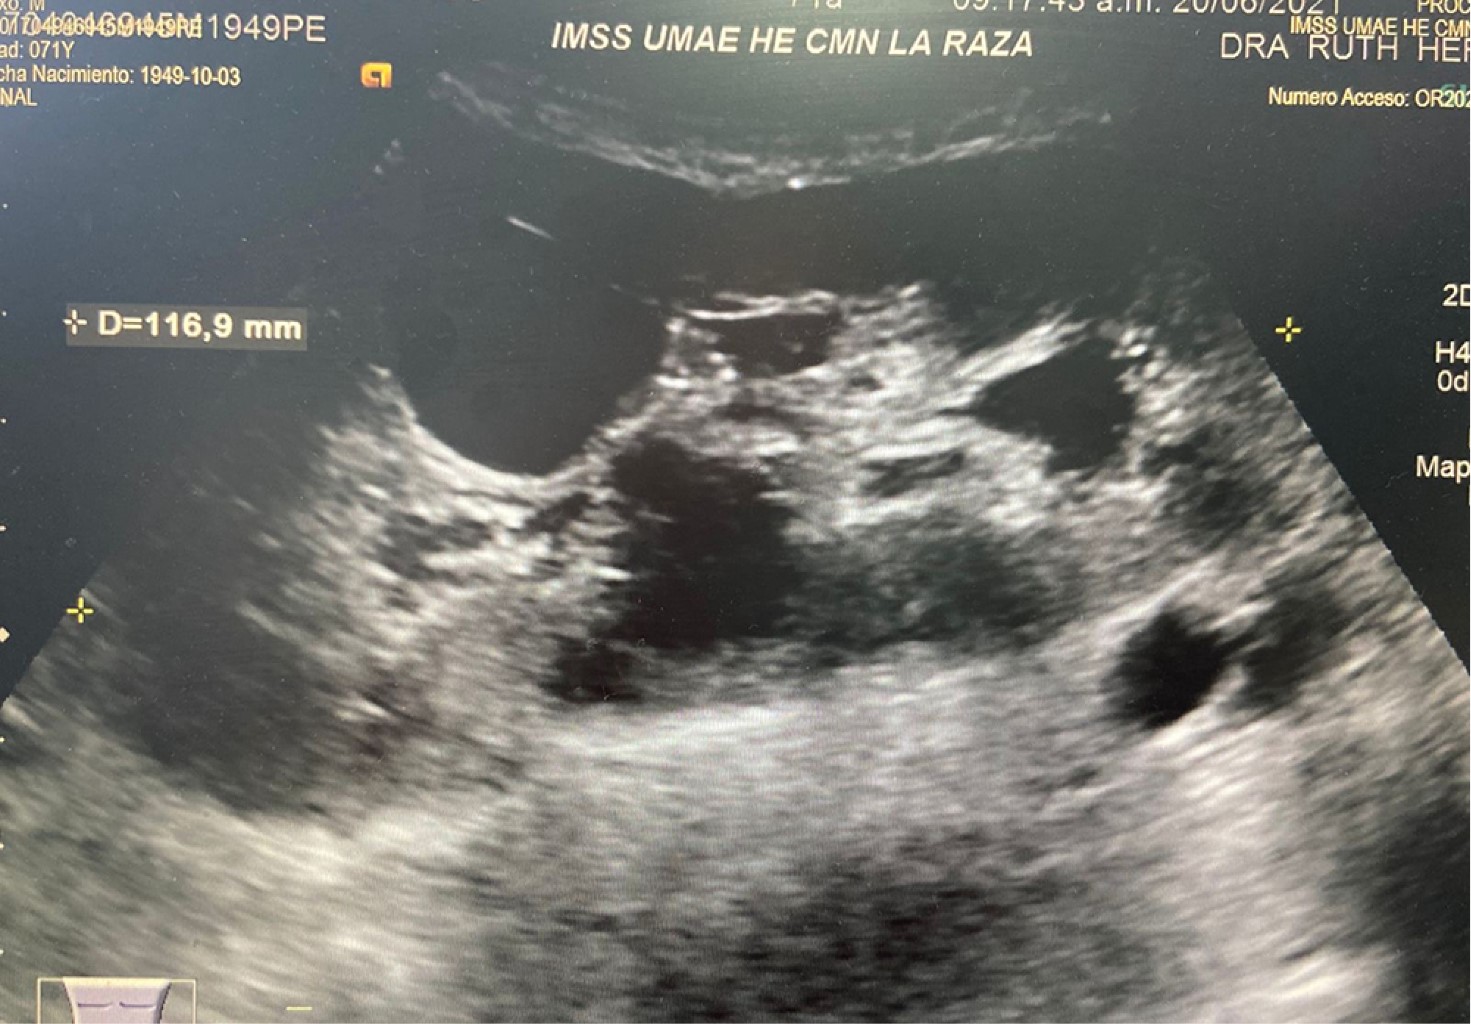

Figure 2